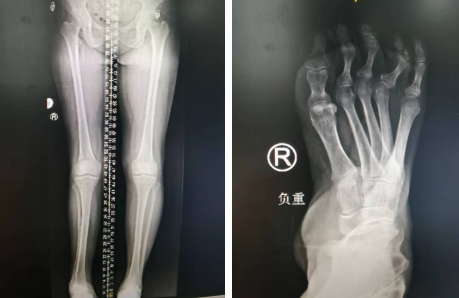

术前摄片

足踝外科张允会副主任医师接待了刘大姐,给她做了详细的专科检查及肌力的评定,询问病史,结合检查结果,诊断刘大姐右足是马蹄内翻足,且右足已经畸形多年,走路时脚不能沾地,需要做矫形手术,将她内翻的右脚放正,才能恢复正常的走路功能。